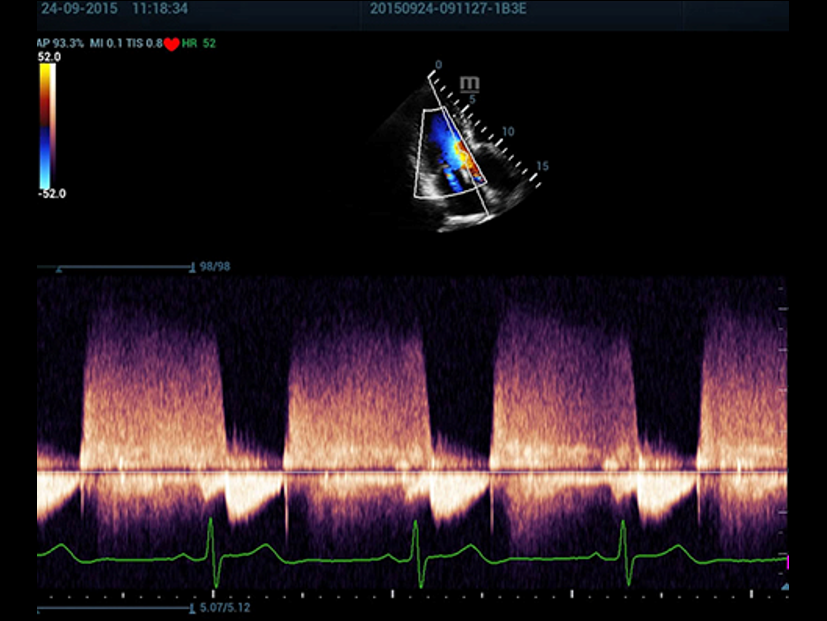

Oltre alla qualit├Ā delle immagini di livello eccellente, Resona 7 migliora anche le capacit├Ā di ricerca clinica il rivoluzionario V Flow per la valutazione emodinamica vascolare, e l'acquisizione piani pi├╣ intelligente dal set di dati 3D per la diagnosi del sistema nervoso centrale fetale. Combinando il pi├╣ intuitivo funzionamento multi-touch basato su gesti e tutte le caratteristiche cliniche essenziali, Resona 7 sta veramente portando nuove tendenze nellŌĆÖinnovazione dellŌĆÖecografia.